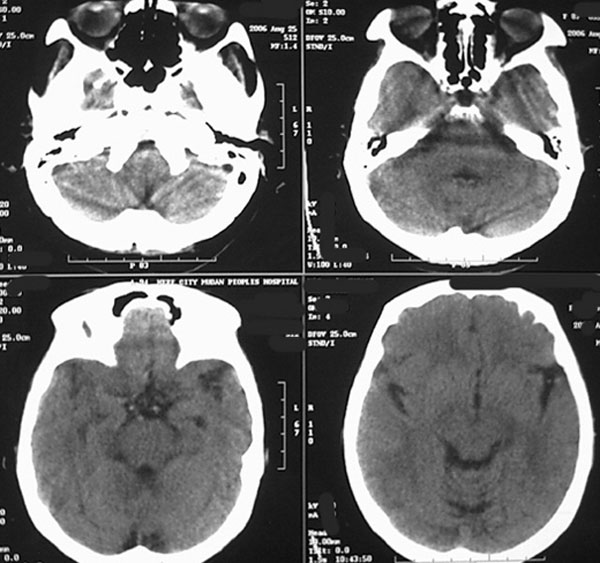

女87左下肢麻木,无外伤史

右颞顶部颅骨内板下新月形混杂密度影,右大脑皮层受压内移,考虑慢性硬膜下血肿,建议增强一下看看病灶,因为平扫好像显示的不是很好;左顶部软化灶

右侧大脑半球脑沟 脑裂变浅或消失,顶叶不规则低密度影,右侧侧脑室明显受压移位,中线偏移,右侧内板下新月形混杂高密度致密影,多考虑:慢性硬膜下血肿.必要时建议强化扫描.

右颞顶部颅骨内板下新月形混杂密度影,右大脑皮层受压内移,考虑慢性硬膜下血肿.

右额颞顶部颅骨内板下方新月形混杂密度影,同侧灰白界限受压内移,右侧脑室呈受压性改变,中线结构左移;左顶叶扫及片状脑脊样低密度区,另可见部分脑沟增宽

ct印象:1.右额颞顶部慢性硬膜下血肿

2.左顶叶软化灶

3.脑部分萎缩

右额颞顶部颅骨内板下方新月形混杂密度影,同侧灰白界限受压内移,右侧脑室呈受压性改变,中线结构左移;应该是右额颞顶部慢性硬膜下血肿,建议mri检查。

右侧颞顶颅内板下可见新月状高低混杂密度影,右侧脑沟回消失,脑组织受压中线结构左移,考虑为右侧慢性硬膜下血肿。病人情况允许可做mri检查。我们遇到过几例没外伤史的病人有硬膜下出血的,多为六七十岁的老年患者,不知慢性硬膜下血肿与年龄有关否?